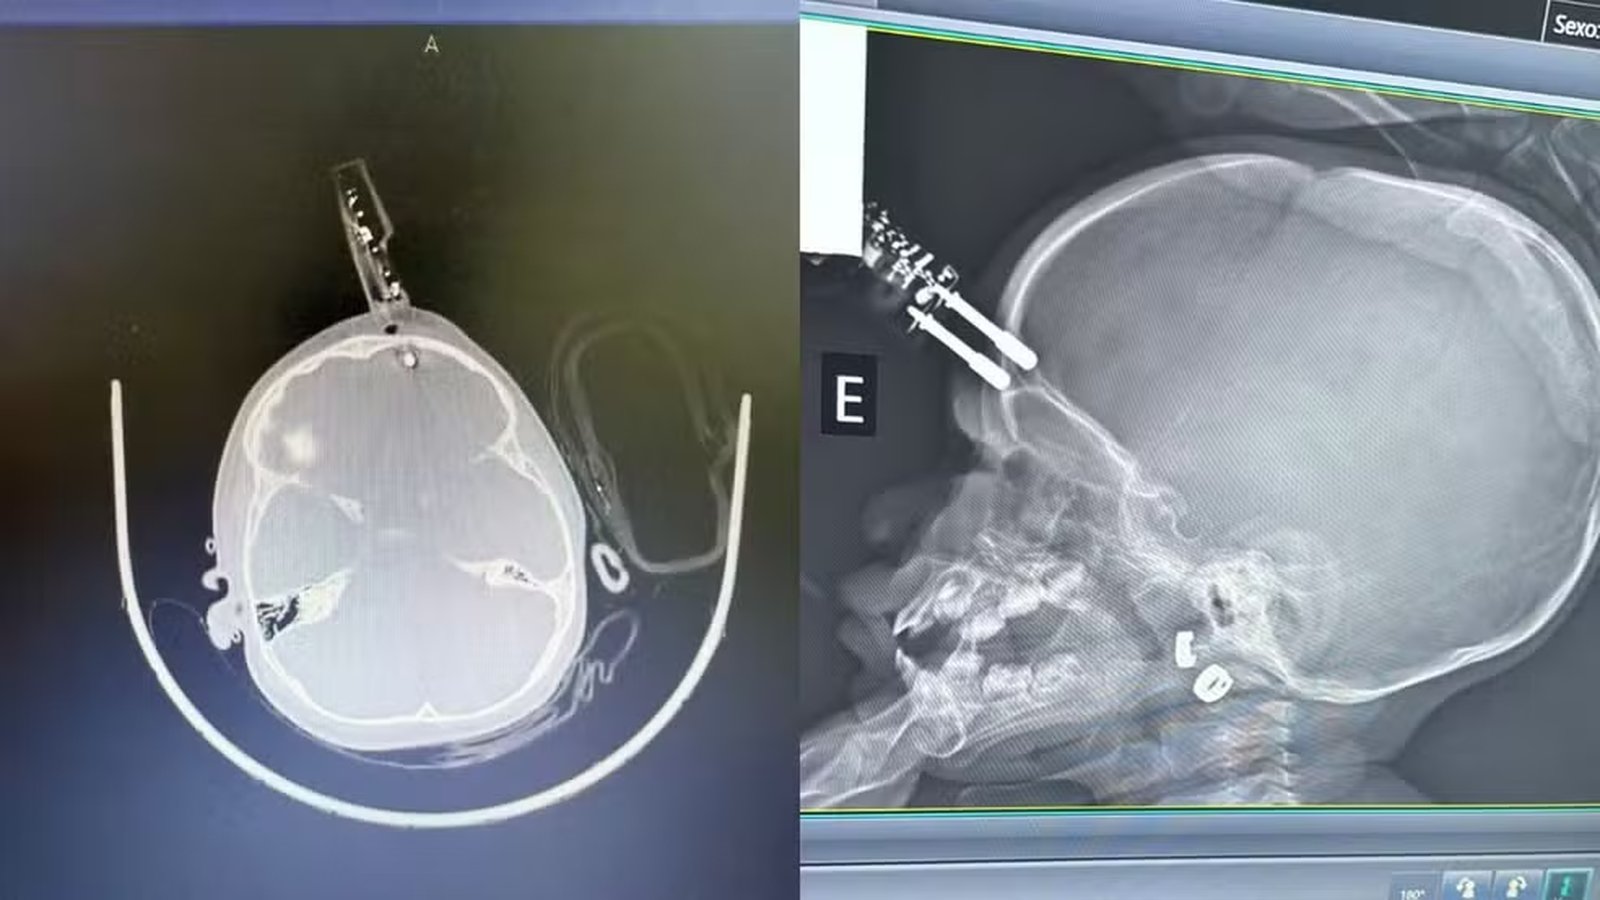

Um acidente doméstico registrado em Divinópolis, no Centro-Oeste de Minas Gerais, chamou atenção de médicos e especialistas na última semana. Uma menina de 1 ano precisou passar por cirurgia após cair da cama e sofrer uma perfuração na região frontal da cabeça causada por um carregador de celular. O caso ocorreu no início de janeiro de 2026, e a criança foi atendida no Complexo de Saúde São João de Deus, recebendo alta médica dias depois.

A principal hipótese levantada pela equipe médica é que a menina estivesse com o carregador na mão no momento da queda. O impacto acabou direcionando o objeto para uma área extremamente sensível do crânio, muito próxima ao olho. Segundo o neurocirurgião que cuidou na paciente, se o objeto tivesse atingido a região ocular, poderia ter causado perda de visão. A resposta rápida da equipe médica foi decisiva para evitar hemorragias ou infecções graves.